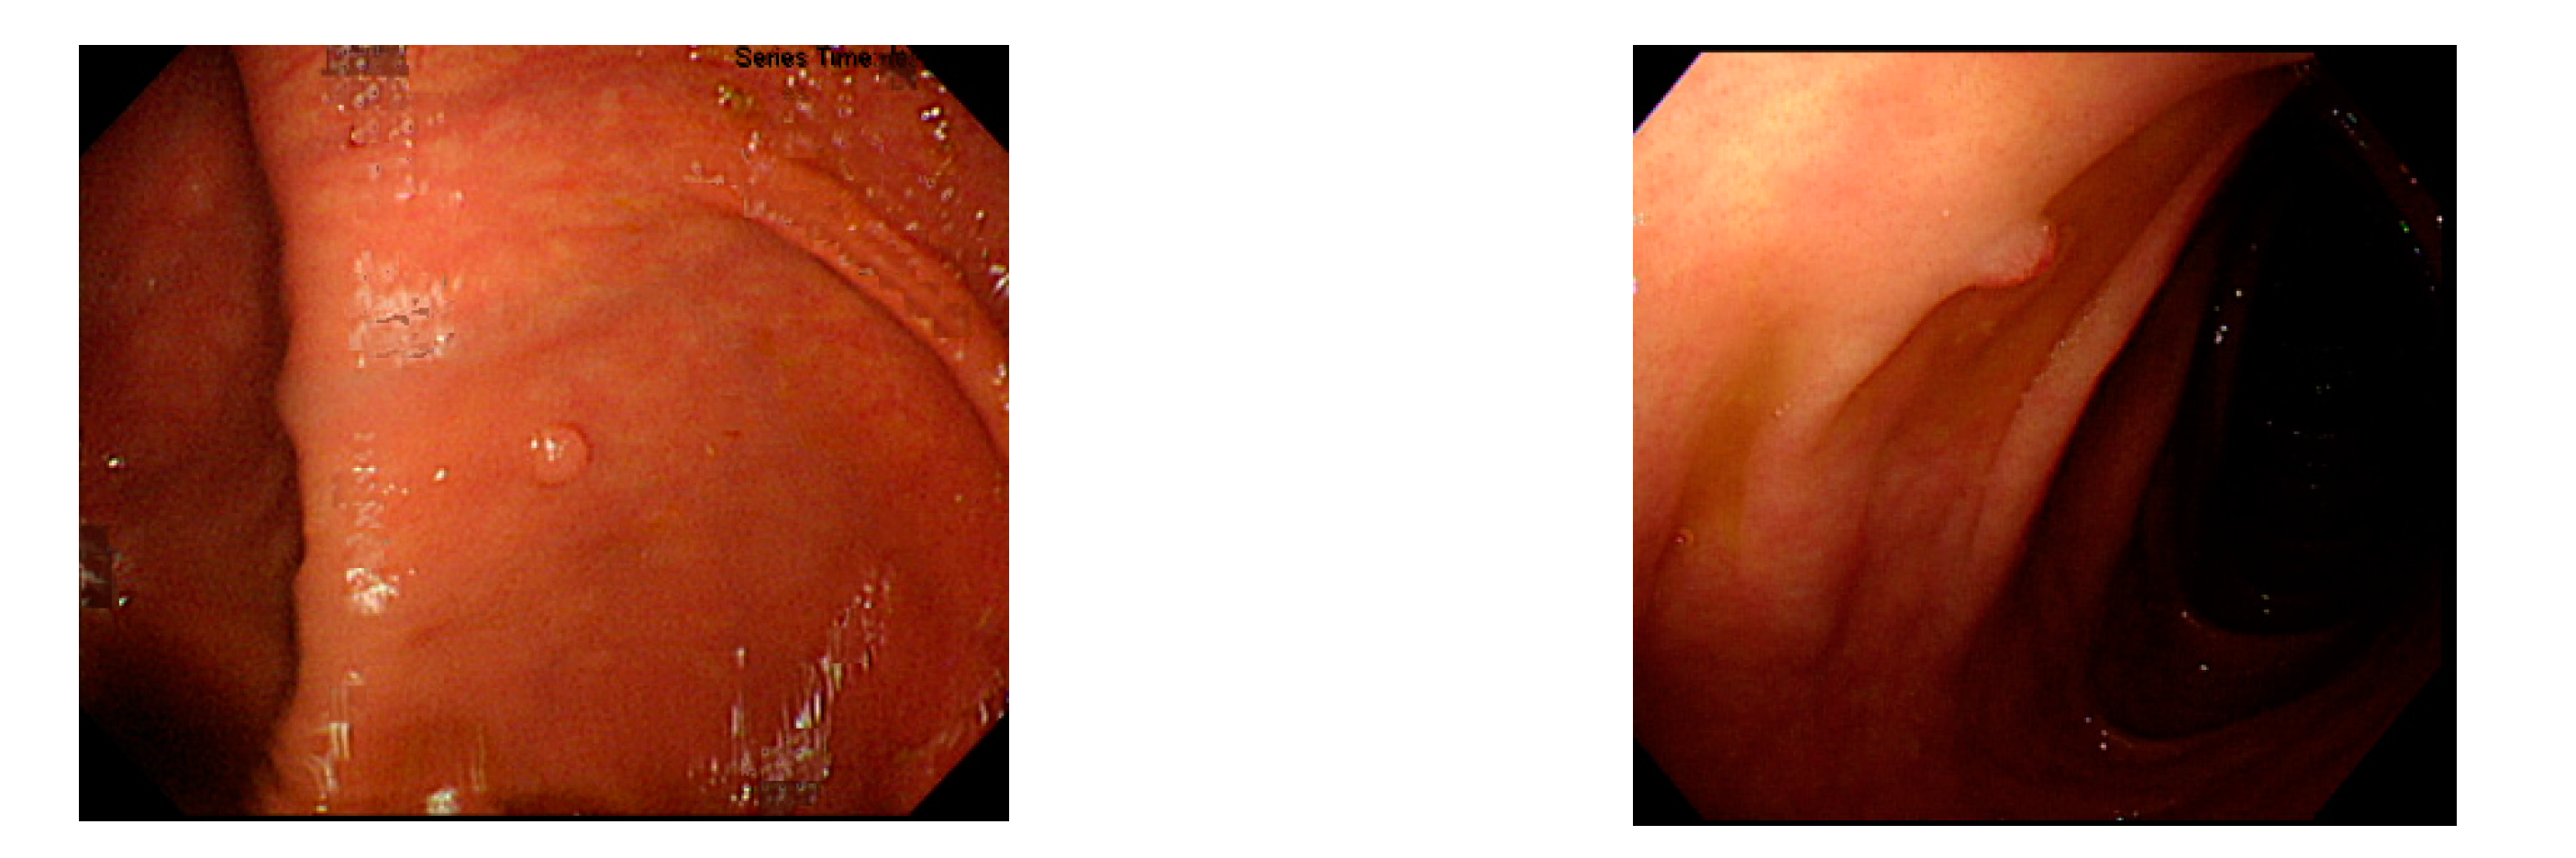

Figure 1.

Example image of NICE classification.

Currently, common magnifying NBI diagnostic classifications are the Sano, Hiroshima, Showa, and Japan narrow-band imaging expert team (JNET) classifications, and the most prevalent non-magnifying NBI diagnostic classification is the NBI international colorectal endoscopic (NICE) classification (Table 1 and Figure 1) [8,9]. In most of these classifications, the histopathology of polyps is determined based on the optical characteristics of lesion color, structure of capillaries, and morphology of capillary surface. The NICE classification, for instance, categorizes colorectal polyps as type 1, hyperplastic polyps; type 2, adenomas, intramucosal carcinoma, or superficial submucosal carcinoma; and type 3, deep submucosal carcinoma. Rectosigmoid diminutive (≤5 mm) hyperplastic polyps are considered as non-neoplastic polyps without malignant potential [8]. The recently developed Workgroup serrAted polypS and Polyposis classification can enhance the diagnostic accuracy of sessile serrated adenoma polyps [10].